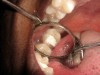

The search for an ideal direct esthetic restorative material is still ongoing. Among the array of RBC materials, some are readily available in the market (flowable, packable, and fiber-reinforced), others have just recently been introduced (siloranes-based), and a few are still in development phase (fluoride-releasing). Individual properties of different RBC materials define their advantages, disadvantages, and clinical uses. Each type of RBC material has its own virtues in some clinical aspects and shortcomings in other aspects. Every material possesses either one or the other ideal properties of a restorative material, but not all of them. Therefore, it is important for a clinician to use every material judiciously and for a clinical application for which it is best suited (Figure 5, Figure 6, Figure 7, Figure 8, Figure 9 and Figure 10).

Figure 6  Clinical applications of RBCs for posterior restorations: occlusal caries restored with silorane-based RBC

Figure 6